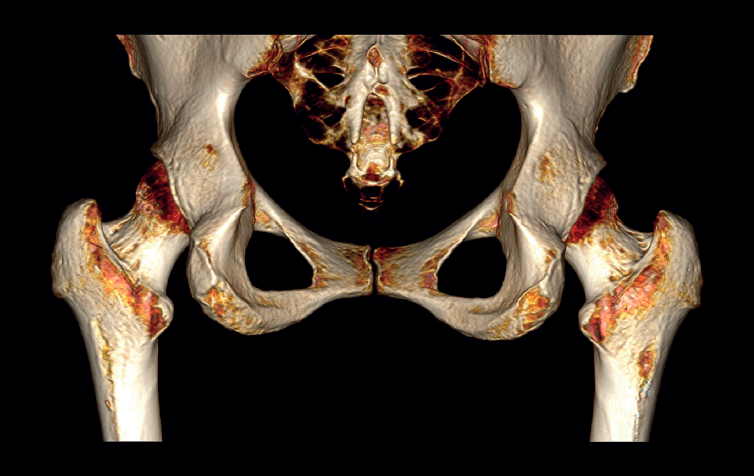

The physical examination revealed a limp-free gait and complete joint balance, with no positive signs of femoroacetabular impingement or inguinal pain. Muscle strength was preserved and similar to that of the contralateral side. She experienced intense pain on palpation of the insertion of the gluteus maximus, referred proximally to the ipsilateral buttock. The pain was reproduced on extension against resistance, and prevented sitting for long periods. Plain radiographic and computed tomography (CT) images revealed calcific tendinosis affecting the aponeurotic prolongation of the gluteus maximus in proximity to its insertion in the upper region of the linea aspera of the femur (Figures 1 and 2) Magnetic resonance imaging (MRI) of the hip showed a labral tear, that proved asymptomatic in the physical examination. In view of the clinical picture of radicular pain, an MRI scan of the lumbar spine and subgluteal space was also performed, ruling out radicular involvement or sciatic neuritis. Her previous treatment over the three years of evolution of the disorder included oral nonsteroidal anti-inflammatory drugs, a specific physiotherapy programme and several ultrasound-guided corticosteroid injections with positive results - though a last session showed no response. Due to the severity and chronicity of the symptoms and their resistance to conservative treatment, surgery was decided to clean and remove the intratendon calcification endoscopically.

Figure 1. Right hip. Posteroanterior 3D CT view showing calcific tendinosis affecting the aponeurotic prolongaation of the gluteus maximus in proximity to its insertion in the upper region of the linea aspera of the femur (arrow).